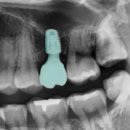

연세 네이처 치과 의원을 발치 후 이제 임플란트를 해야 하기에 1주일 정도 후에 예약을 잡고 방문을 하였다. 대부분 임플란트 후기를 찾아보면 다 의사들이 적은 내용으로 과정 설명 아프냐 안 아프냐 내용은 찾아보기 어려웠다. 실제로 체험을 하거나 수술을 받은 블로그는 거의 없었다. 발치를 하고 임플란트를 해야...